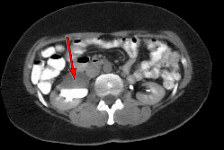

FINDINGS: The ultrasound (not shown) demonstrated dilated collecting system versus extrarenal pelvis on the right. Fig. 1 and Fig. 2 are nephrographic and delayed images through the kidneys. They demonstrate a large dilated right renal pelvis (red arrows) with urine-contrast level and a normal-sized ureter consistent with UPJ obstruction. Fig. 3 is a 3D image from a renal MRA showing an accessory right renal artery (yellow arrows) supplying the right lower pole and impressing upon the right UPJ, explaining the UPJ obstruction. Normal renal arteries are also clearly seen (green arrows)